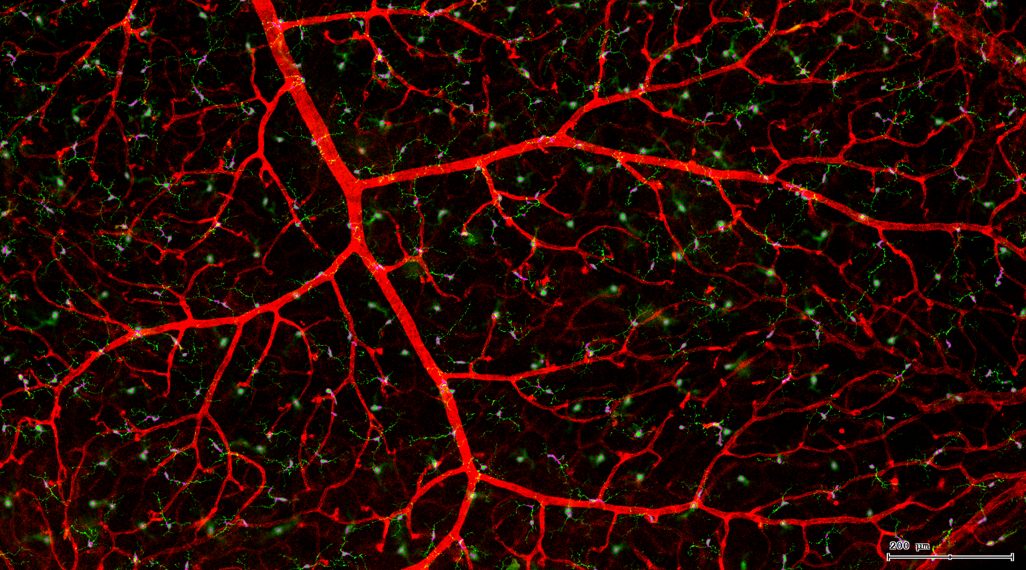

视网膜荧光样本中小胶质细胞胞体、神经纤维识别、血管识别、血管斑点识别、神经元与血管的距离分析。

5. 识别血管的Texa Red染色区域面积及强度。

血管识别:根据Texa Red通道进行识别,并去除面积小的及非同一焦面的血管,仅对确定的清晰的同一焦面的大血管进行面积统计。

血管与小胶质细胞的距离0-0.1μm(红色框线标记)

血管与小胶质细胞的距离0.1-1μm(粉色标记)

血管与小胶质细胞的距离1-3μm(粉色标记)